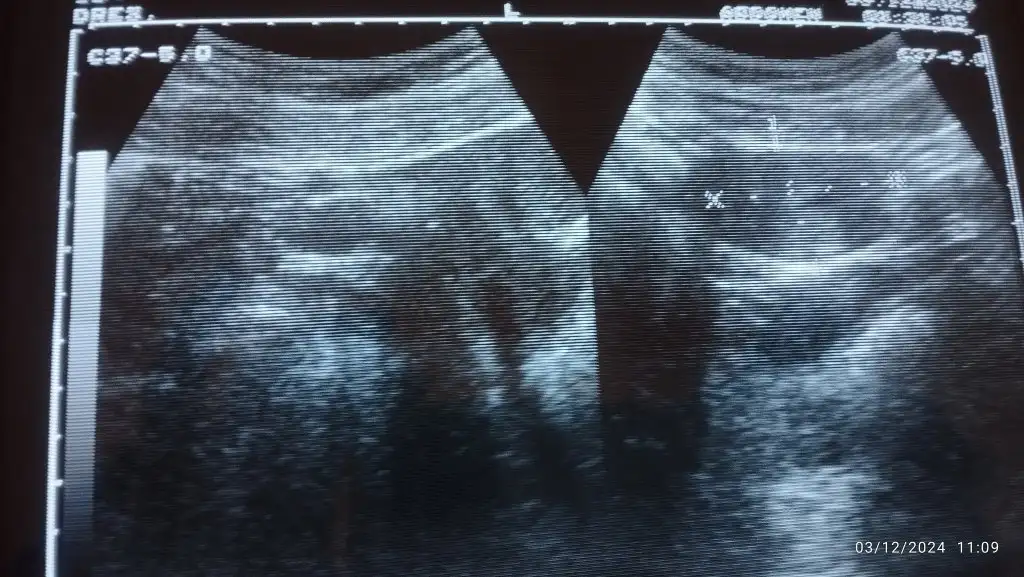

Acaba resim geldimi bi bakarmisinizkese 3000 ken gözükür seninki üç gün önce bu değere ulaşmadığı için görünmemiştir ama bugünkü değerine göre görülürdü keşke bugün baktırsaydın için rahat ederdi

Kese görünümü var canım inşallah sağlıkla yolk sac ve bebeği kalp atışlarını görürsün 2 hafta sonra merak etmeAcaba resim geldimi bi bakarmisiniz

İşaretlenmiş zaten bı artıdan diğerine olan kısım bebişin kesesi sağlıkla gelsin minikAcaba resim geldimi bi bakarmisiniz